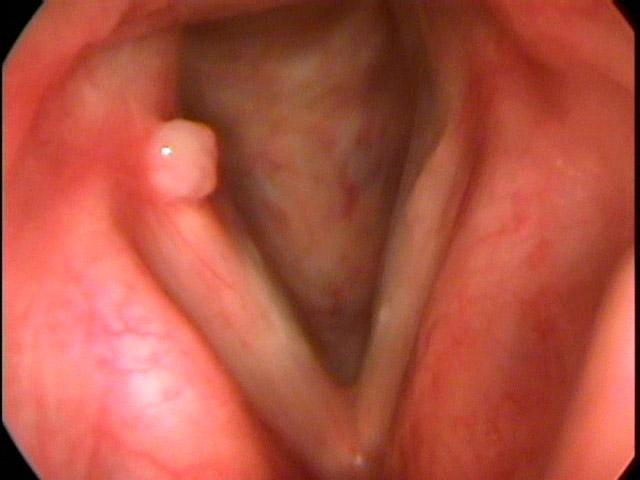

O câncer de orofaringe, como é chamado, pode se desenvolver em áreas como amígdalas, base da língua e parte posterior da garganta. Segundo especialistas, além dos fatores genéticos e exposição ao HPV, algumas práticas comuns entre mulheres têm sido associadas ao aumento dos casos.

Mulheres que mantêm relações orais sem proteção com parceiros infectados pelo HPV estão em risco, mesmo que o vírus não apresente sintomas visíveis no parceiro. O vírus pode se alojar na mucosa da garganta e, com o tempo, provocar alterações celulares que resultam em tumores.

Ficar atenta a sintomas como dor persistente na garganta, dificuldade para engolir, rouquidão e caroços no pescoço pode ser o primeiro passo para um diagnóstico precoce. Mulheres que apresentam esses sinais devem procurar um otorrinolaringologista ou oncologista o quanto antes.